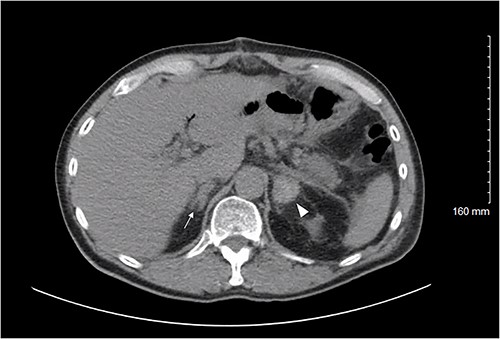

On POD 8, he presented with severe abdominal pain and CT demonstrated an ileus without evidence of postoperative complication. He was readmitted and gradually improved over the next 3 days but continued to experience intermittent abdominal pain and inconsistent bowel function. Therefore, on POD 11 a CT was repeated, demonstrating a new high density 2.6 × 2.6 cm left adrenal collection consistent with subacute hemorrhage (Fig. 1). The right adrenal gland appeared more prominent although not as striking as the left. Findings were consistent with BAH.

Axial CT abdomen/pelvis on POD 11 demonstrating the left adrenal gland (white arrowhead) with a high density 2.6 × 2.6 cm fluid collection; density is consistent with a subacute bleed. The right adrenal gland (white arrow) demonstrates thickening suggesting a small hemorrhage, less pronounced than the left.